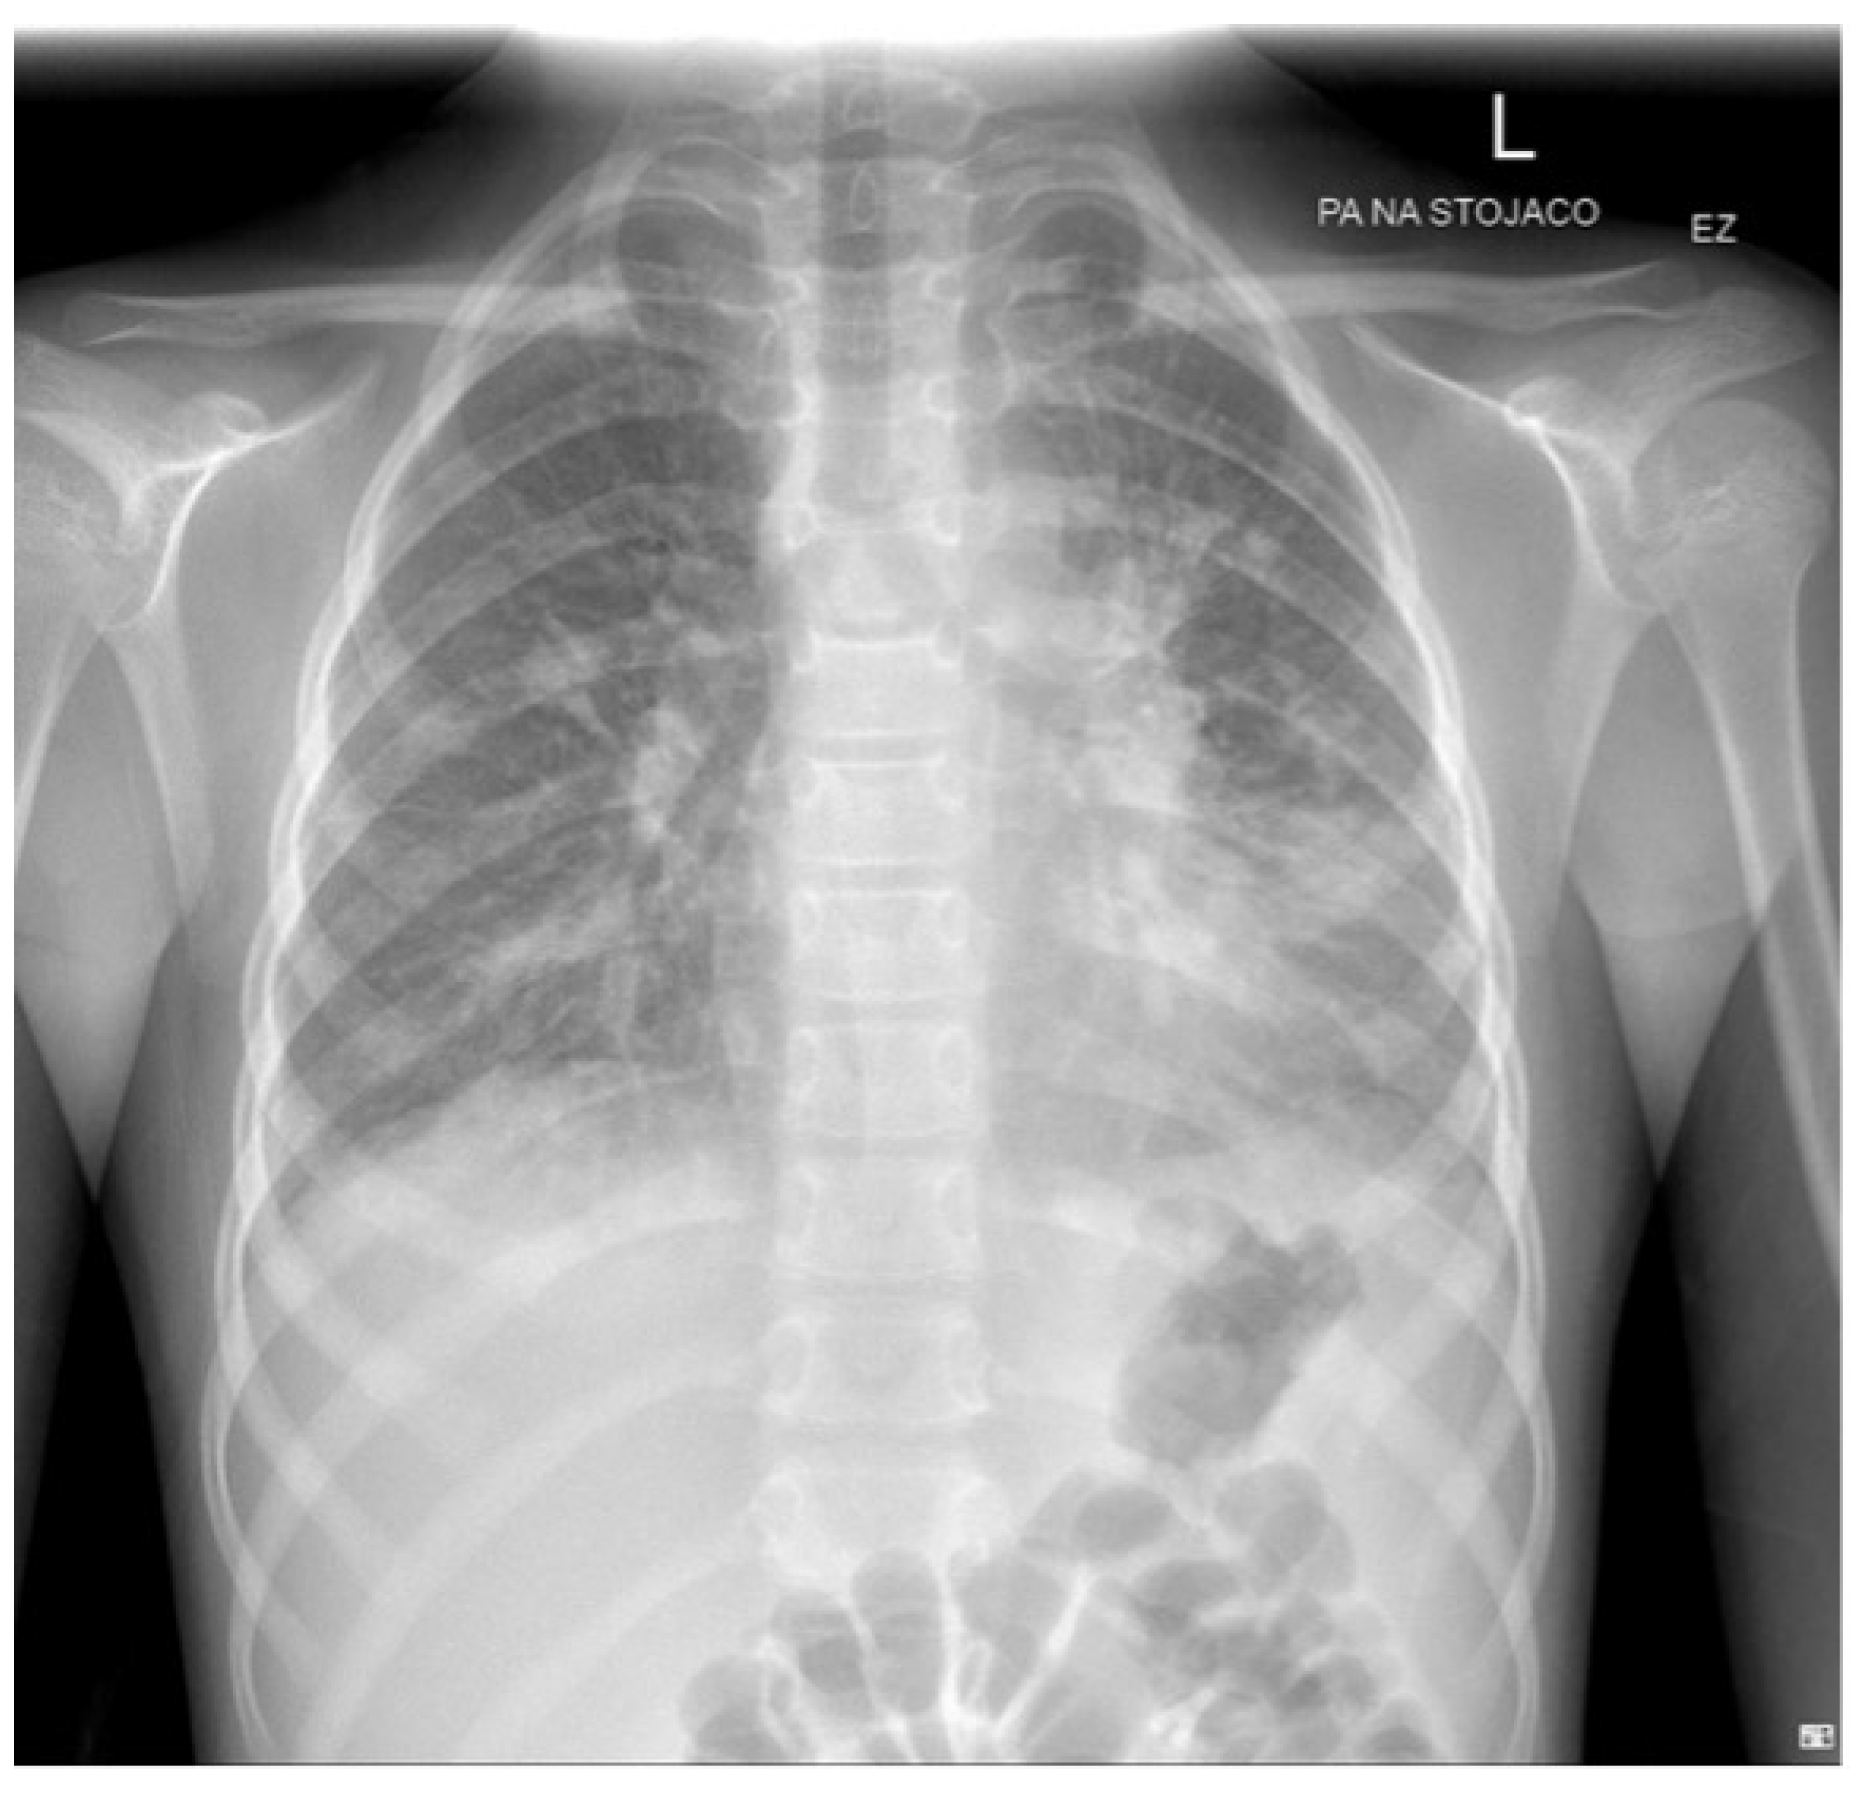

2. Case Report